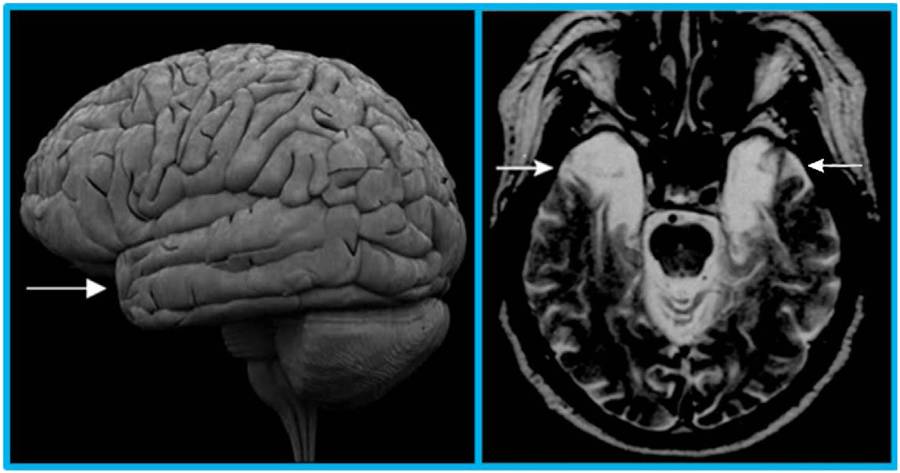

Wearing先生脑组织中感染的病毒破坏了他的下丘脑和下丘脑附近的区域,因此导致失忆症。 另一个叫Henry Molaison的病人同样丧失了部分记忆,因为医生在手术中移除了他的下丘脑和颞叶区的顶端部分(图1)。这些研究表明,大脑中的下丘脑和其邻近的颞叶区对产生和获取长期记忆起到至关重要的作用。

图1. H.M.患者在接受手术移除颞叶区后的脑扫描图。 左图中反映的是大脑外观的侧面图。 图中箭头指的是颞叶区的顶端。右图中是H.M.患者脑切面图,视角是从下往上观察。 箭头指出的颞叶区中较亮的部分是手术后残留的液体。因为移除了颞叶区那部分,H.M.患者再也不能回忆起手术前几年内发生的事情。此图来自参考文献[2]。